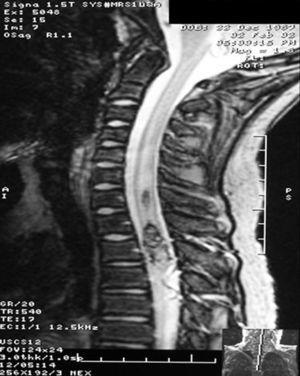

La causa malformativa incluye 2 pacientes (12,5 %) afectados de una malformación arteriovenosa medular de localización C2-C6 en un caso y D6 en el otro. El primero se presentó con cervicalgia que precedió a la tetraplejía mientras que en el segundo el síntoma inicial fue dolor en el hombro que fue seguido por paraparesia. A ambos se les administró metilprednisolona entre las 9 y las 19 h de la lesión y se realizó radiología intervencionista al cuarto día (figs. 1 y 2). Se realizó traqueostomía al paciente con lesión cervical a los 19 días de ingreso. Ambos residen en su casa, uno de ellos con ventilación mecánica domiciliaria.

Figura 1.RM: malformación vascular medular.